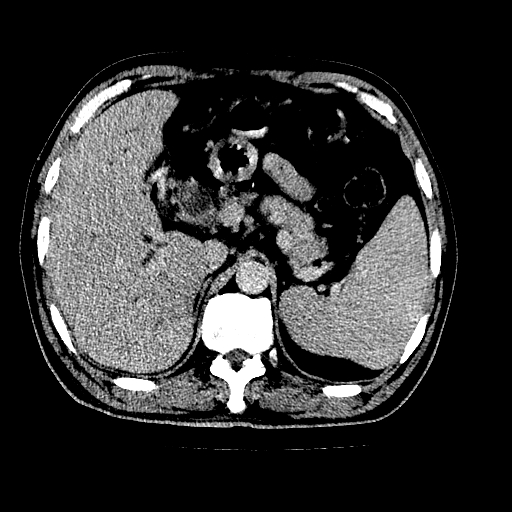

男,66岁,上腹部不适、黄染一周。彩超示:肝左叶占位,肝内胆管扩张,胆总管扩张,胆总管占位?

象胆管细胞癌,但又没有看见明显强化结节,陶瓷胆囊,十二指肠及胆总管显示不清晰,难下定论。

肝左叶不规则软组织肿块影,边缘不规整邻近肝实质受累分界不清;肝内胆管(左叶)明显扩张成“软藤状”,诊断:肝左叶胆管细胞癌。

胆囊缩小,其内胆汁浓缩,也提示梗阻部位应该位于胆囊管起始部以上或是胆囊管受累及,支持肝外胆管癌。